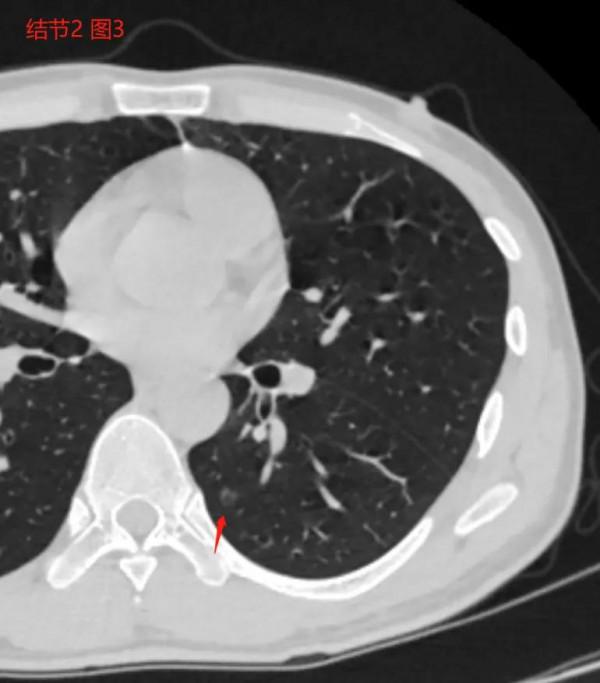

8月9日,因為發燒為了排除新冠進行胸部CT,偶然發現三個肺結節,當時是感冒,血象高,沒有咳嗽症狀,口服了6天莫西沙星片之後再沒有經過其他特殊治療。結核感染T細胞試驗陽性,三次結核菌痰塗片陰性。以前沒有被診斷過肺結核,但是親戚中有肺結核患者,從小跟肺結核親戚有過多次接觸。本人從小都比較瘦,目前身高173cm,體重55公斤。9月14日和11月14日複查一次胸部CT,變化不明顯。請問戴主任,我這種情況是否需要直接手術?可以再抗炎治療2周後間隔2周複查胸部CT之後再根據複查結果決定是否手術不?需要診斷性抗結核治療不?謝謝戴主任幫忙看下。

三個結節文字報告圖片如下:

2022年1月19日CT文字報告: